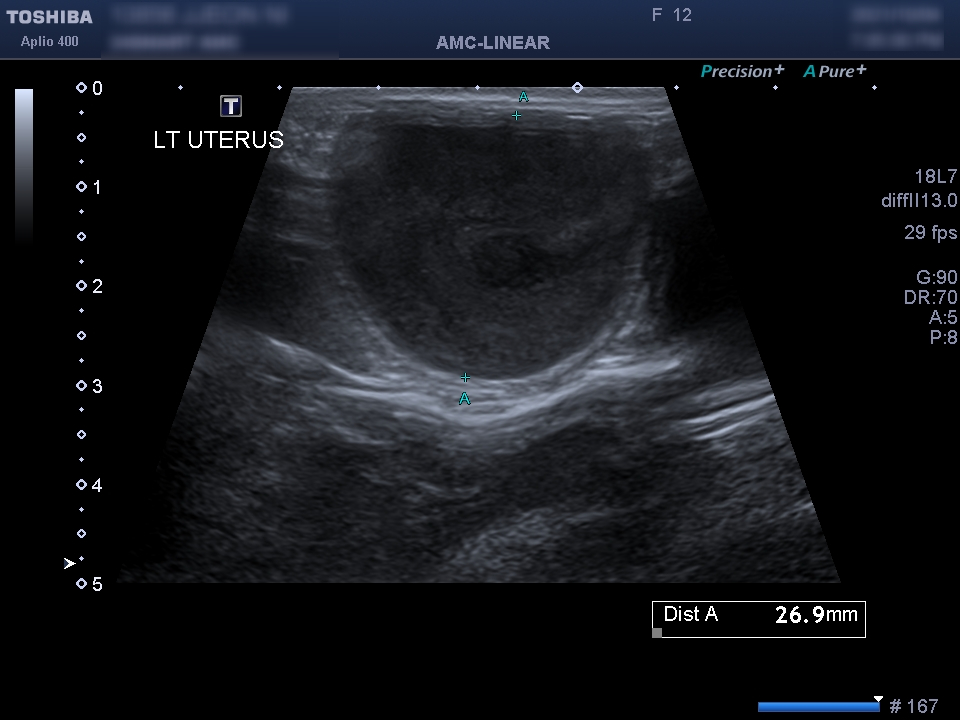

신체 검사 결과 생식기 쪽에서 삼출물이 확인되었습니다.자궁 축농이 의심되는 상황이어서 초음파 검사를 통해 확진을 할 수 있었습니다.

초음파 검사를 통해 확장되어 있던 양쪽 자궁을 확인할 수 있었습니다